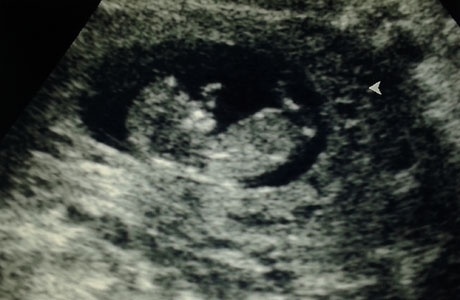

Az első napokban, természetesen, elmentünk egy magán ultrahangos vizsgálatra. Órákkal előtte gombóc volt a torkomban és összeszorult a gyomrom. Az iker elvesztése óta nem találkoztam a kicsivel, és az előző vizsgálaton talált majdnem 5 centis ciszta a petefészkemen is aggasztott.

Ahogy a baba képét megláttam a monitoron, ösztönösen a szívverését kerestem, és meg is találtam. „Charlie” 5,74 centiméteres óriási méretekkel rendelkezik a feje búbjától a popsijáig, és minden a lehető legnagyobb rendben vele. Morcos kedvében volt, mivel a szonográfus próbálta piszkálni, hogy felkeljen és mozgolódjon egy kicsit. Durcásan lökött magán egyet, majd hátat fordítva visszaaludt. Hihetetlen, hogy mennyire picike, mégis emberszerű, ha lehet egyáltalán így fogalmazni.

A vizsgálatra a családom női tagjai kísértek el. Mivel jövő héten, otthon is lesz egy ultrahang, a férjem úgy gondolta, hogy most átadja a „terepet” a csajoknak, hadd bűvölje el őket gyermekének látványa, és majd jön velem inkább jövő héten. Nagyon úgy tűnt a felvételeken, hogy a csajos „buliba” egy kukis is belecsöppent, hiszen a 4D-s vizsgálat közben közölték velünk, hogy úgy néz ki, hogy „Charlie” kisfiú. Persze mivel még nagyon korai lenne ezt 100%-osan biztosra mondani, ne éljük bele magunkat túlságosan.